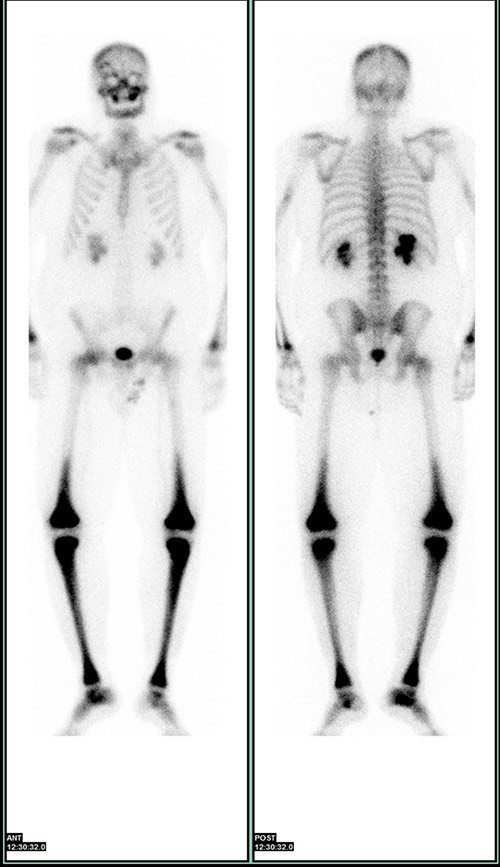

Røntgenundersøkelse av de lange rørknoklene viste symmetrisk utbredt sklerose i diafyser og metafyser, med utsparing av epifysene i radius, ulna, femur og tibia (fig 5). I tillegg var det tegn til periostitt, mest uttalt i femur og i tibia. Ved skjelettscintigrafi var det kraftig aktivitetsopptak i distale del av femur, proksimale og distale del av tibia, distale del av radius og i maksillen bilateralt (fig 6). Endokrinolog fant ikke holdepunkter for diabetes insipidus eller andre endokrine forstyrrelser.

Sykdommen rammer menn hyppigere enn kvinner, og gjennomsnittlig debutalder er 55 år (16 – 80 år) (5). Mange organer kan bli affisert av sykdommen (tab 1) (5, 6). Nesten alle pasienter med Erdheim-Chesters sykdom har affeksjon av skjelettet, men bare omkring halvparten har symptomer på dette og da som oftest som smerter i knær og ankler. Typiske radiologiske funn er bilateral og symmetrisk osteosklerose i diafysen og metafysen til de lange rørknoklene, oftest i underekstremitetene. 99technetiumskjelettscintigrafi og 18FDG PET-skann vil vise økt opptak i disse områdene (7) – (9).